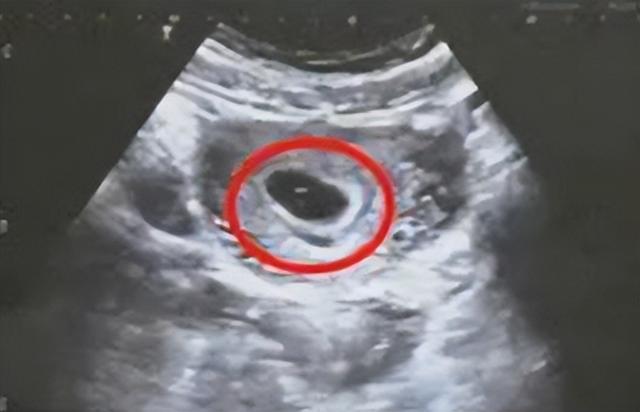

空孕囊是什么原因造成的呢?(hcg24万出现空孕囊揭秘空孕囊形成的7大原因)

备孕夫妻最开心的事情就是怀上了。“五周左右去医院检查的时候还好好的,让过2周去复查,结果hcg2.4万左右,B超没有看到卵黄囊和胎芽,医生说可能是空孕囊…… ”空孕囊是什么?首先我们要知道,女性怀孕以后受精卵植入子宫...